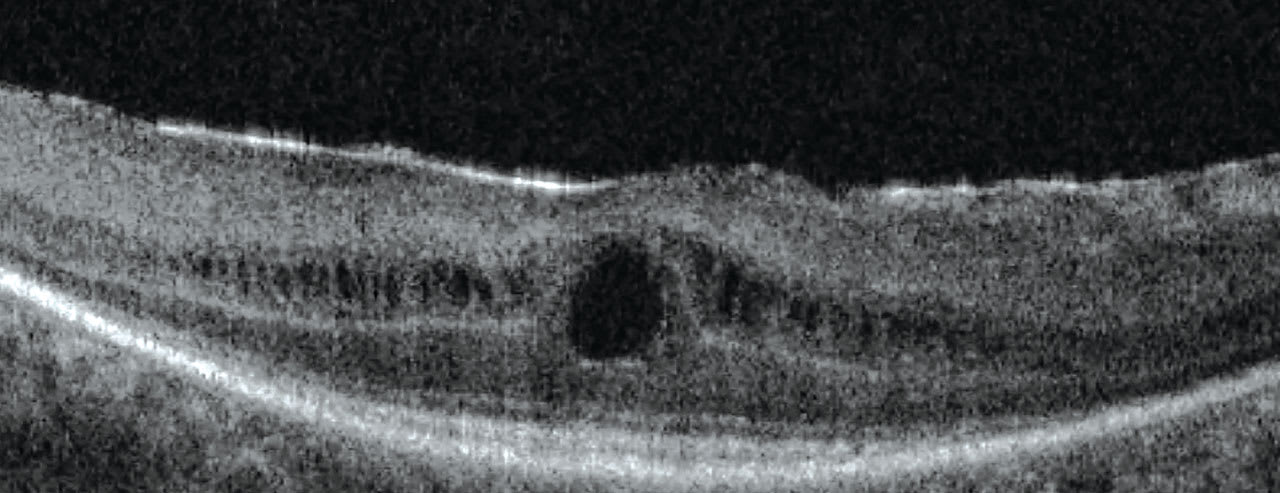

When his BCVA seemed to be stuck around 20/30 in his new scleral lenses, a macular optical coherence tomography (OCT) revealed bilateral macular edema (Figure 1). Wide-field retinal imaging also showed a reduction in peripheral retinal vessels. The patient was referred to a retinal specialist and a fluorescein angiography was performed; unfortunately, he was diagnosed with retinitis pigmentosa in addition to his recently treated keratoconus.